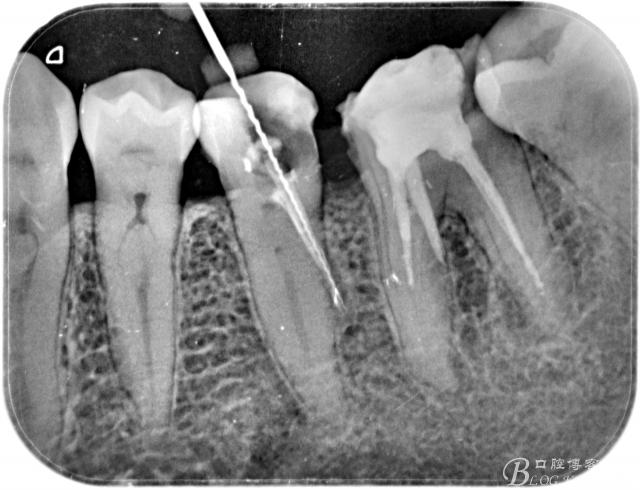

一例前磨牙根管侧穿再治疗!

弯曲冠部的内侧牙本质和弯曲根尖部的外侧牙本质(如上图),造成侧穿